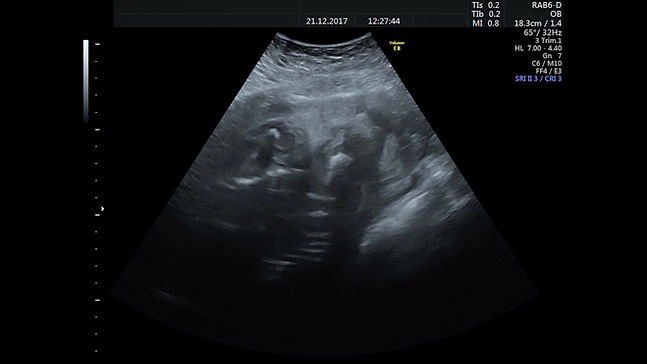

2D Ultrasounds

SureScan Studio in Roscommon provides accurate, clear and timely 2D pregnancy scans in a quiet, private setting. We offer early reassurance scans, gender scans, and wellbeing scans, giving you a closer look at your baby during pregnancy. All scans are carried out by trained professionals using reliable equipment in a comfortable space.

We offer early scans from 6 to 15 weeks. These help confirm a pregnancy, check the heartbeat, and estimate your due date. We understand early pregnancy can bring worry. That’s why we provide clear answers with no fuss. Our 2D scans show the gestational sac, yolk sac and foetal pole clearly on screen.

We use 2D imaging to provide clear, live feedback. You’ll see your baby on screen while we talk you through what we’re checking. We also offer printed scan photos to take home.